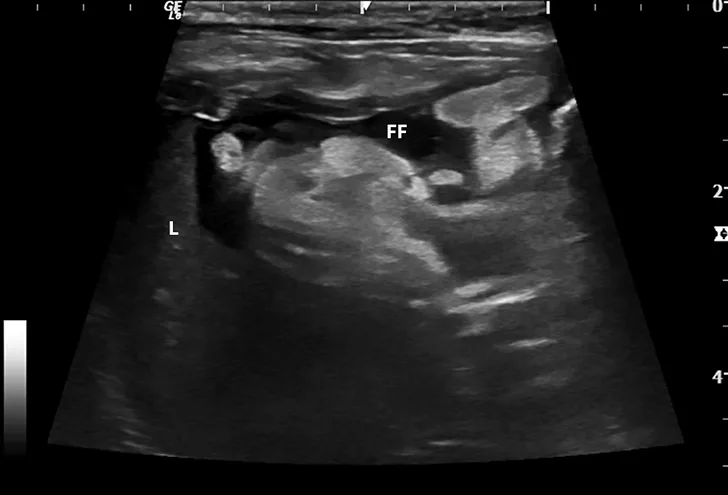

Dry FIP can manifest with organ dysfunction, uveitis, neurologic signs, fever, anemia, and/or lethargy and is caused by granulomas or immune complex deposition. Cats with wet FIP may have ascites or pleural effusion in addition to the aforementioned signs (Figure 1). Clinical presentation can vary from minor to life-threatening and involve almost any organ system.

FIGURE 1

Ultrasound image showing abdominal effusion in a cat with wet FIP. Anechoic fluid is present between organs, distending the abdomen. FF = free fluid; L = liver; S = spleen; K = kidney